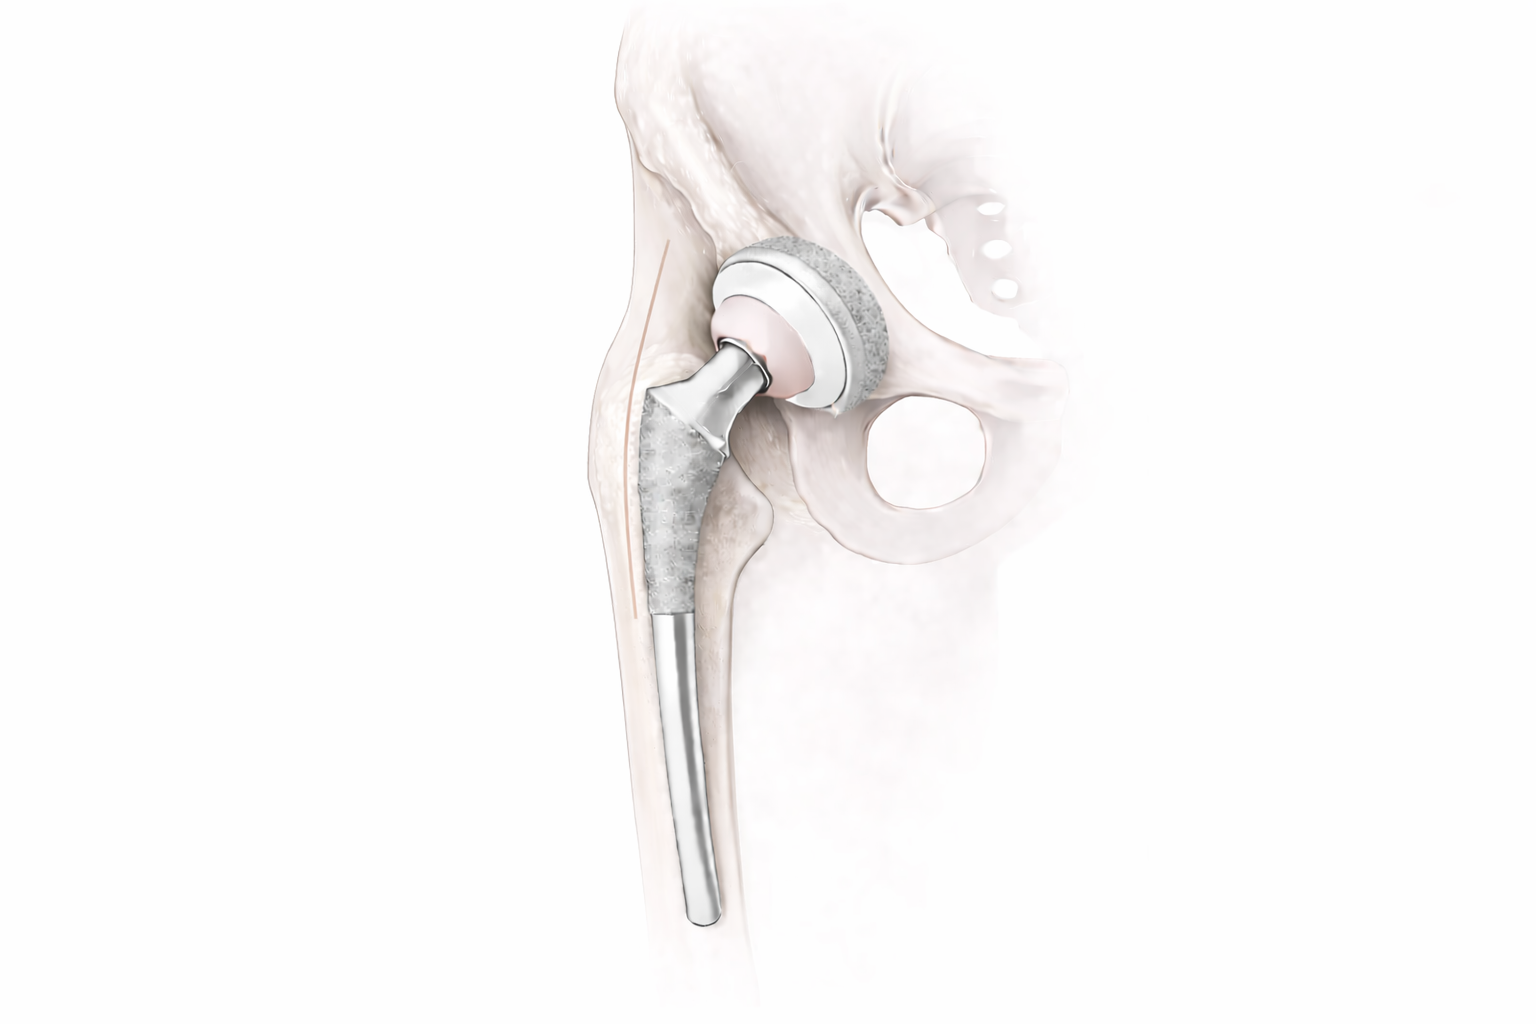

Medical illustration of anterior hip replacement showing implant positioning in the pelvis and femur.

Total hip replacement removes damaged cartilage and bone from the hip joint and replaces them with precision-engineered components designed to restore smooth, stable motion.

In appropriate patients, the procedure is performed between muscles rather than splitting or detaching them. Preserving surrounding soft tissue may support early mobility and stability within a structured recovery plan.